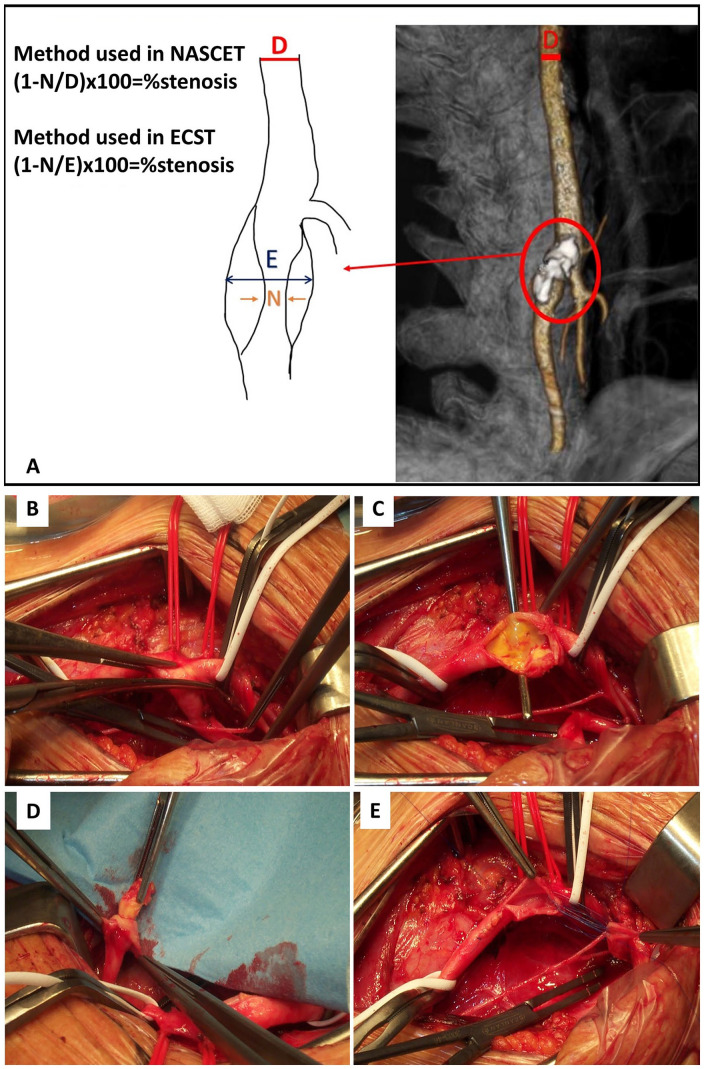

Design: The GTB-VD recruits patients undergoing surgical repair for carotid artery stenosis (CS) and abdominal aortic aneurysm (AAA), enrolled on the basis of selection criteria and subdivided for pathology and type of intervention, upon informed consent.

Results: From 2018 to the end of 2023, 442 CS (distinguished into severe-asymptomatic or symptomatic, displaying a ratio of 5:1) and 214 AAA have been collected. CS is more frequently associated with diabetes and peripheral artery diseases, AAA with pulmonary history, and renal function impairment. Open surgery is more used for CS and endovascular for AAA.